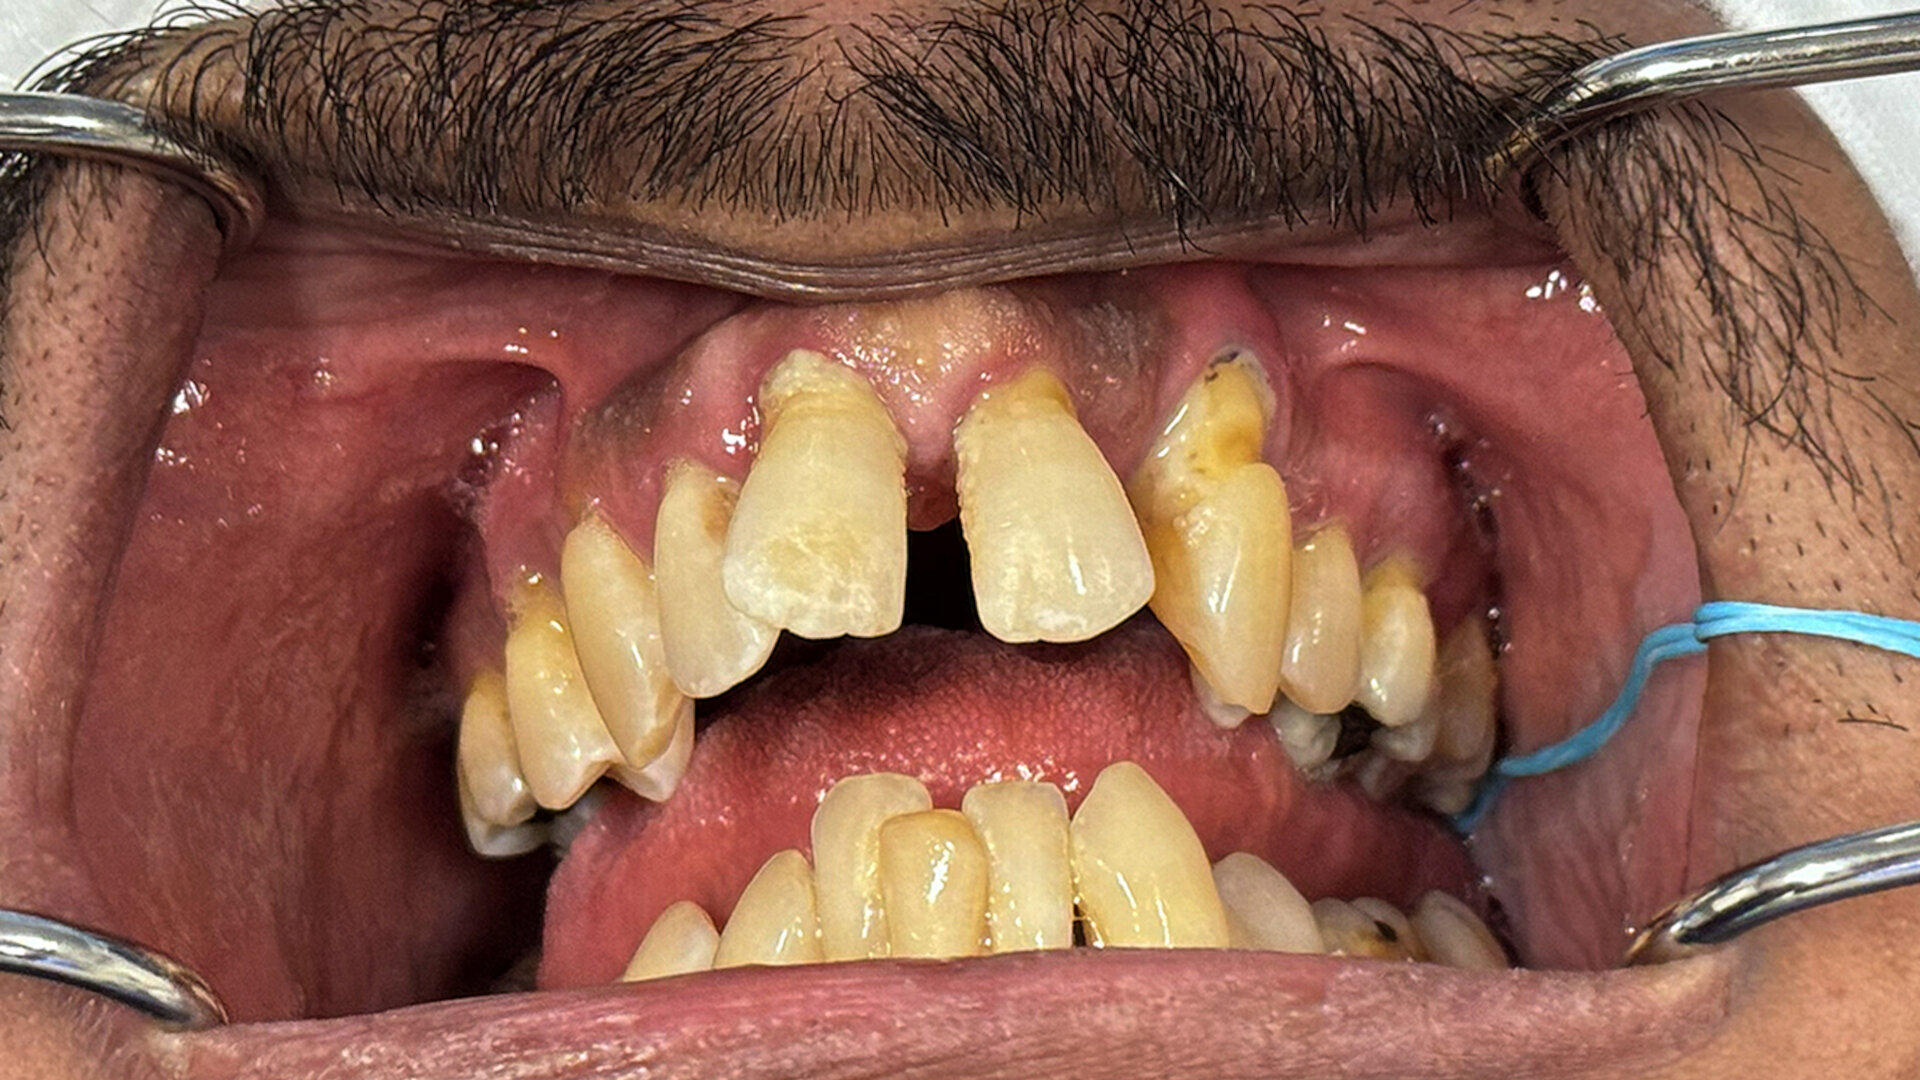

Fig. 1b: Pre-op situation. Intra-oral retracted view of the maxillary and mandibular teeth in occlusion.

A 49-year-old male patient presented with failing maxillary and mandibular teeth. The findings of the clinical and radiographic examinations were severe periodontal disease, generalised bone loss, anterior spacing and tooth mobility, in addition to overall poor hygiene maintenance (Figs. 1a & b & 2a). The patient was informed of the findings, and several treatment options were discussed, including complete and/or partial dentures, implant-supported overdentures and implant-supported fixed restorations. After discussion regarding the options, the patient decided on full-arch implant-supported fixed restorations.